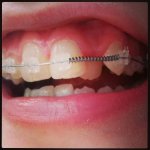

Бамп. Не хотеть зуб на зуб как пикрелейтед. В такой ситуации, лицо точно удлиннится же.

Если на пол зуба, ок я согласен, ебало не вытянется. Но если зуб на зуб как пикрелейтед, олошадинится же все.

Ну ты ж смотри, чтод аже на твоем пике, передние зубы не смыкаются, нижние чуть-чуть позади. Да и вот мне делали на ползуба, как там брекеты делают не знаю.